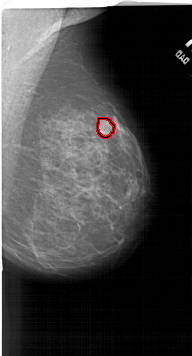

A_1515_1.RIGHT_CC

RIGHT_CC LINES 6556 PIXELS_PER_LINE 3496 BITS_PER_PIXEL 12 RESOLUTION 43.5 OVERLAY

FILE: A_1515_1.RIGHT_CC.OVERLAY

TOTAL_ABNORMALITIES 1

ABNORMALITY 1

LESION_TYPE MASS SHAPE LOBULATED MARGINS ILL_DEFINED

ASSESSMENT 4

SUBTLETY 2

PATHOLOGY BENIGN

TOTAL_OUTLINES 1

BOUNDARY